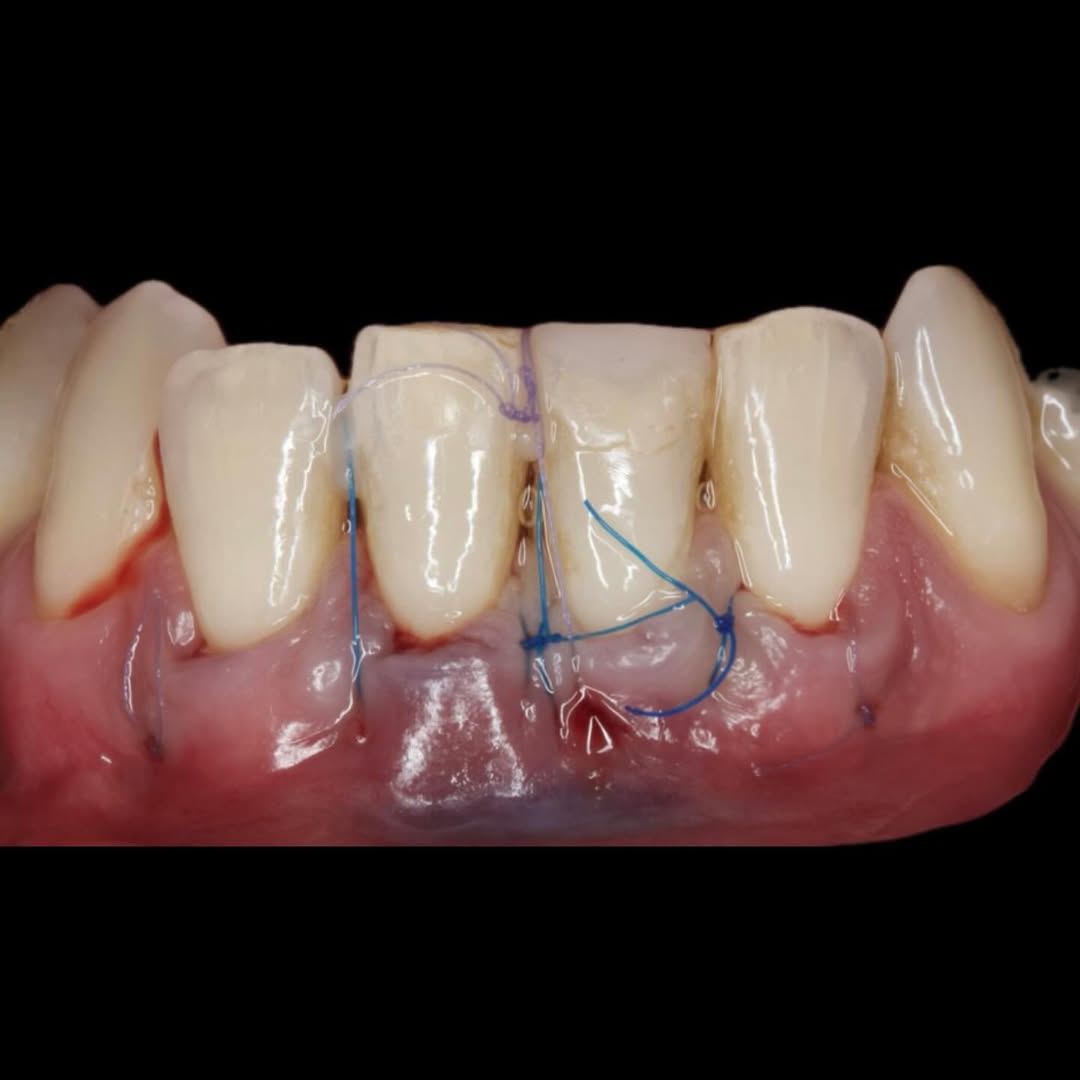

Durante una mañana, asistirás a una Cirugía Mucogingival de recubrimiento radicular de recesiones múltiples en IV y V sextante (36 a 43).

Gracias al uso del microscopio y a la proyección en tiempo real en pantalla, verás exactamente lo mismo que veo yo durante la cirugía, sin tener que estar

Podrás asistir a la planificación de casos y cirugía de injerto de tejido conectivo. Factores determinantes y elección de la técnica adecuada. Sumérgete en un protocolo predecible y técnicamente correcto para obtener resultados óptimos.

Aprende la planificación y técnica de la cirugía Mucogingival para el recubrimiento de recesiones y aumento de banda queratinizada en el sector anteroinferior

La formación comenzará con la presentación del caso clínico que se abordará durante el curso, seguida de una cirugía en directo, que permitirá observar paso a paso el procedimiento y la toma de decisiones clínicas. Durante la jornada se profundizará en los conceptos biológicos aplicados a

Durante una mañana, asistirás a una Cirugía Mucogingival de recubrimiento radicular de una recesión unitaria en 31 con frenillo asociado. Gracias al uso del microscopio y a la proyección en tiempo real en pantalla, verás exactamente lo mismo que veo yo durante la cirugía, sin tener que estar